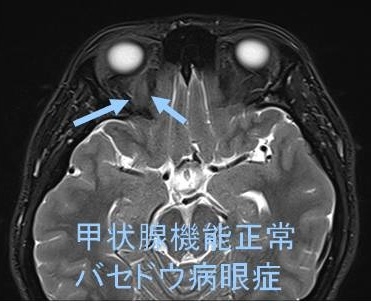

長崎甲状腺クリニック(大阪)では、メルカゾール(5mg)0.5T/日投与により数年間、甲状腺機能正常を維持している安定したバセドウ病患者にいきなり遅延型バセドウ病眼症が起こりました。そのMRI画像がこれです。